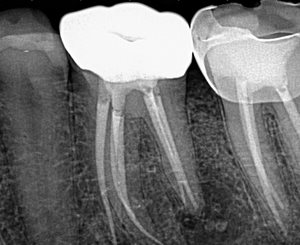

When I see a lateral radiolucency on the furcation side of a mesial root of #19 or #30 (Fig 1: around the junction of the middle and apical 1/3), I highly suspect a middle mesial (MM) canal that exits laterally.

Re-treatment was performed, and the MM canal was identified, instrumented and obturated. The final radiographs show that the lateral lesion corresponds with the MM canal and its lateral exit point (Fig 3 and 4).

Procodile Q™ files were helpful in instrumenting all 5 canals—and for removing gutta percha during the re-treatment of the previously obturated canals—due to their reciprocating motion when they meet resistance!